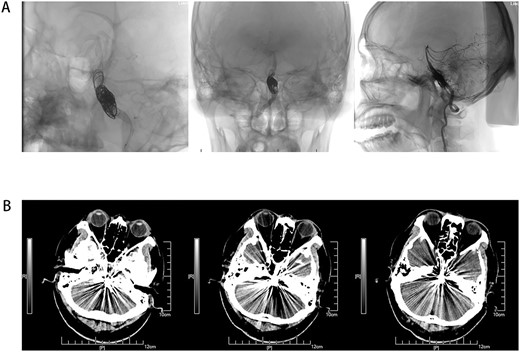

Male, AA, 44 years old, admitted in July 2022 with recurrent pain on the left side of the maxillofacial region for ~1 year. In the last 6 months, the dose of carbamazepine was increased to 300 mg three times daily, but the control of facial pain was still unsatisfactory, so the patient and his family numbers requested to be hospitalized for surgery. The patient had a history of hypertension for ~15 years. The maximum blood pressure was ~200/120 mmHg. The nifedipine controlled-release tablet was used to control his blood pressure by 30 mg daily, which is maintained at ~140/80 mmHg. The neurological examination on admission was unremarkable. TN was assessed as grade V according to the Bar row Neurological Institute classification. Magnetic Resonance Imaging (MRI) of the head suggests small ischemic focus in the pons and cerebellum; marked extending of the basilar artery (Fig. 1A–C). To clarify the etiology, doppler ultrasound of the carotid and vertebral arteries bilaterally revealed no atheromatous plaque or hemodynamics abnormalities. An electrocardiogram and cardiac function and cardiac ultrasound were performed. The results were normal. Biochemical tests for blood cell count, liver function, kidney function, and glucose test revealed no abnormalities. The Digital subtraction angiography (DSA) was given to the patient (Fig. 2A and B). Antiplatelet aggregation therapy with a combination of clopidogrel and aspirin was used before operation. The DSA displayed the VBD, the VBD was length 2.5 cm and width 9 mm, its path was tortuous and deviated to the left. Normal blood flow in the middle venous phase of the imaging was normal. Stent-assisted interventional embolization was chosen. A suitable coil was selected to form basket by EV3 (20 mm*50 cm, Medtronic, USA) and the stent catheter was withdrawn and repositioned through the coil into the right posterior cerebral artery. Release stent 1: LEO (5.5 mm*60 mm, LEO, USA), then choose the appropriate ring (14 mm*30 cm, 13 mm*30 cm, 12 mm*30 cm, 10 mm*30 cm, Taijie Weiye, China) to occlude the dilated artery (Fig. 3A). Postoperatively, we scanned the Computed Tomography (CT) (Fig. 3A), the TN was completely relieved, but there was residual left-sided facial palsy with a House-Brackmann grade IV and a grade III right limb muscle strength. Systematic treatment was operated at the rehabilitation unit, once the condition was stabilized. At 3 months post-operative follow-up the patient showed significant improvement in muscle strength in the right limb, with muscle strength grade V− and significant improvement in facial palsy, which was graded House-Brackmann grade II.

(A) Coil and stent implantation for VBD, and show peripheral blood supply after operation. (B) Non-contrast axial CT scan of the brain showing VBD after surgery.